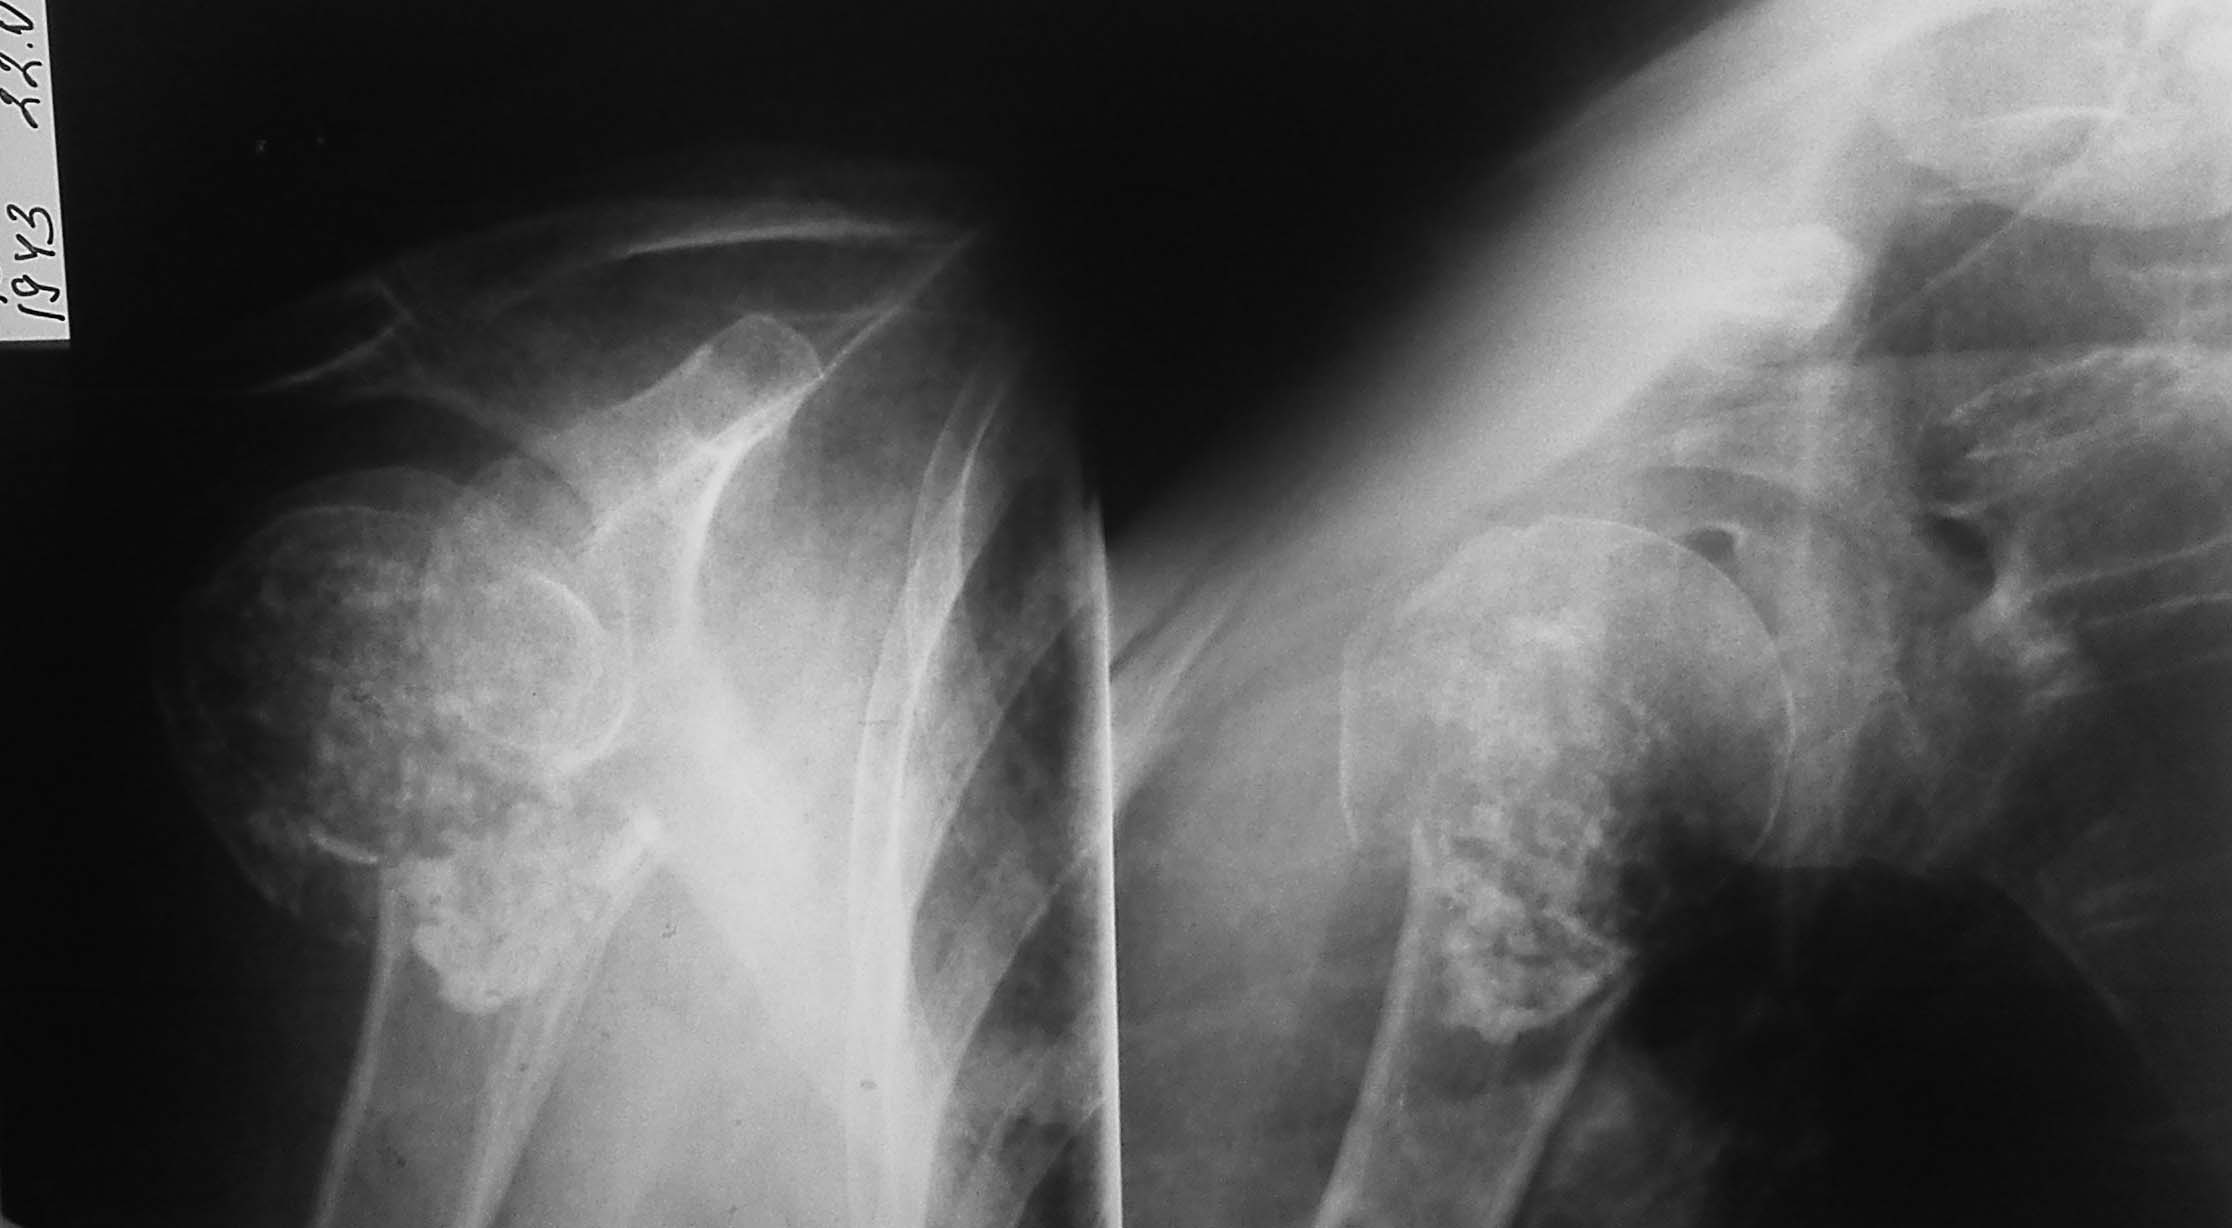

Уважаемые коллеги, помогите найти клинику для коллеги! В отделении на лечении находится наша коллега - физиотерапевт 67 лет с новообразованием головки и патологическим переломом плечевой кости. По КТ - новообразование - энхондрома, гистологически - хондрома. По нашему мнению, пациентке требуется эндопротезирование плечевого сустава. Подскажите - куда можно обратиться в столице по этому вопросу, чтоб получить квоту и прооперироваться. Интересует ЛПУ, в котором выполняется эндопротезирование плечевого сустава по квотам. Будем признательны за любые советы и идеи. Очень хочется помочь коллеге.